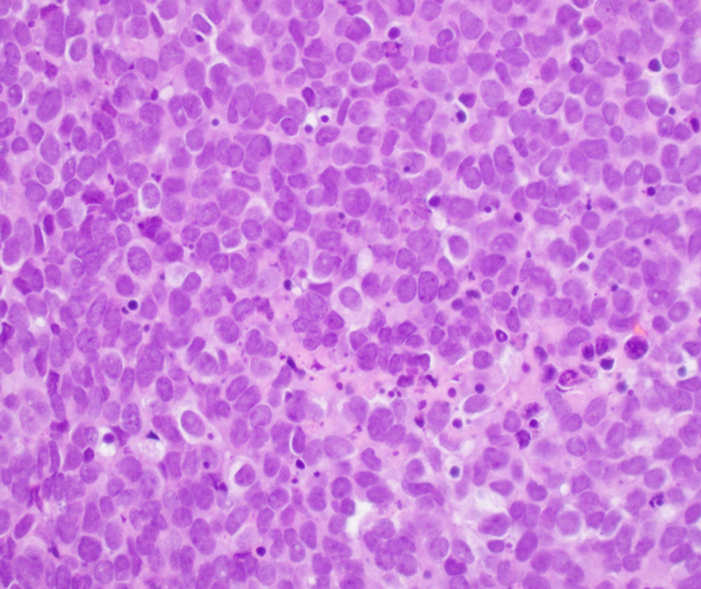

Microscopic (histologic) description

- Classical Ewing sarcoma (Virchows Arch 2009;455:397)

- Uniform small round cells

- Tumor cells 1 - 2x size of lymphocytes

- Round nuclei

- Finely stippled chromatin

- Inconspicuous nucleoli

- Scant clear to eosinophilic cytoplasm

- Indistinct cytoplasmic membranes

- Sheet-like growth pattern

- Islands separated by dense fibrous tissue

- Subset with neuroectodermal differentiation (Homer-Wright pseudorosettes)

Microscopic (histologic) images